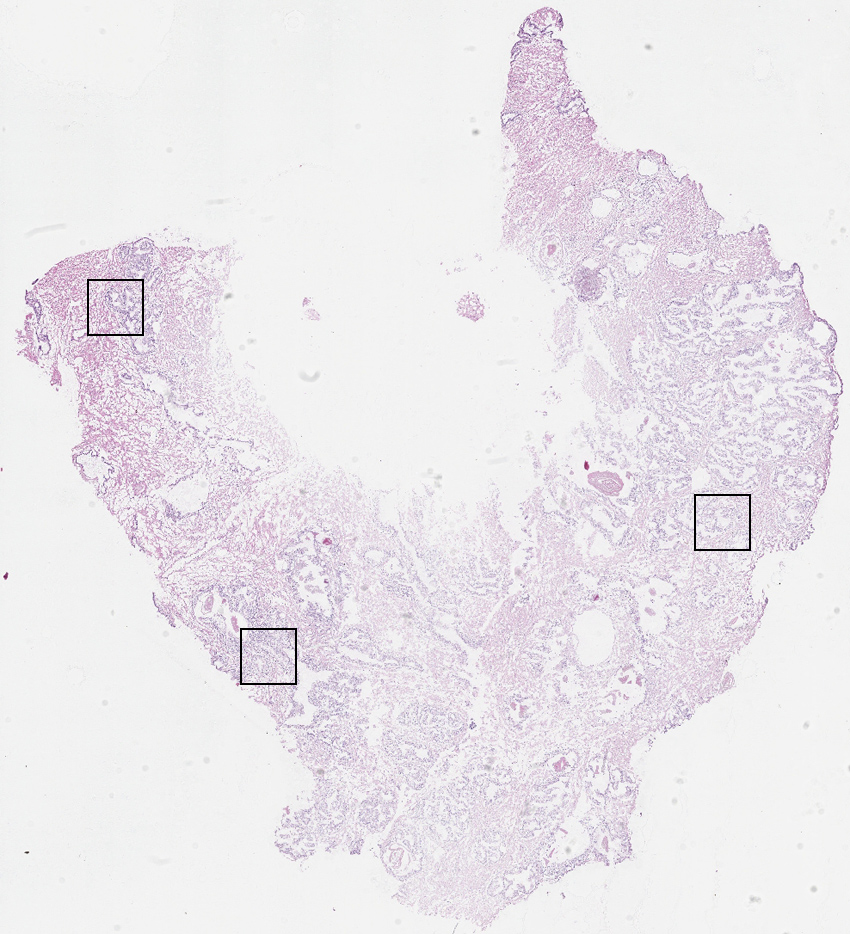

Cell types%

Glandular cells:

60

Smooth muscle cells:

35

Other cell types:

5